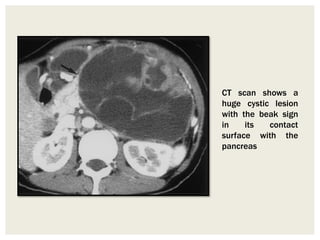

Beak Sign

When a mass deforms the edge of an

adjacent organ into a “beak” shape, it is

likely that the mass arises from that

organ.

On the other hand, an adjacent organ

with dull edges suggests that the tumor

compresses the organ but does not

arise from it

CT scan shows a

huge cystic lesion

with the beak sign

in its contact

surface with the

pancreas